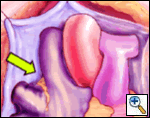

Take great care that all atrial tissue medial to the pulmonary veins is ablated. This may occasionally require a second energy application passing the bipolar clamp from caudad to cephalad to ensure a complete electrical isolation.

Never ablate on the pulmonary veins as pulmonary vein stenosis could ensue. Take great care to ablate only atrial tissue.